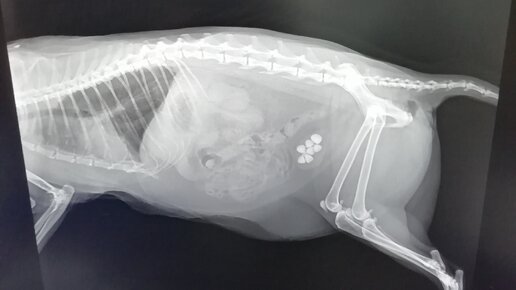

Проблемы с мочеиспусканием у котов.

Здравствуйте, сегодня поговорим, о такой распространённой проблеме, как осложнения мочеиспускания у котов. Проблемы с мочеиспускания бывают разные: частое мочеиспускание - полиурия, задержка мочеиспускания - анурия, мочеиспускания с кровью - гемоурия и так далее. Причины этих проблем различны, начиная от стресса, и заканчивая нарушением работы почек. Почти во всех случаях у котов появляется цистит - воспаление мочевого пузыря. Стоит быть готовым к тому, что полноценного лечения заболеваний мочевыводящих...